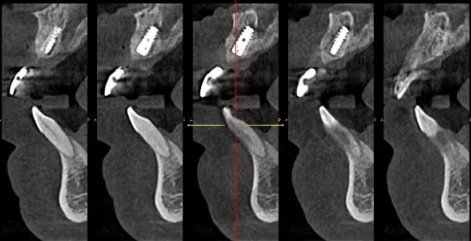

项目介绍:无锡佳士洁口腔于2018年开业,院内特色项目是种牙,开展舒适种植、即刻种植、数字化种植、All - on - 4半口/全口无牙即刻负重等多项种植技术,采用德国精工标准的数字化种植系统,德国瓷睿刻CEREC即刻修复系统等精良设备。种植医生有甘恒木、郭峰、张永喜等。价格方面,经典金属托槽牙齿矫正9790元起,金属自锁矫正10790元起,时代天使隐形矫正17790元起,数字化舒适种植牙6870元起,全瓷贴面1970元起,爱尔创全瓷牙冠2490元起。

项目介绍:无锡维乐口腔隶属于美维集团,是大型口腔连锁机构,在无锡有3家分店。口腔正畸是其明显优势,拥有MBT直丝弓矫治、陶瓷托槽半隐形矫治、美国隐适美无托槽隐形矫正、舌侧隐形矫正等特色技术。种植方面,有One - Day Apple即刻种植技术,6小时就能长新“牙”,1天就可以吃苹果,费用低且种植时间短。医生团队包括徐剑虹、伍江英等口腔正畸医生,以及黄旭光等种植医生。价格上,金属托槽矫正7970元起,正雅隐形矫正15790元起,时代天使隐形矫正18790元起,韩国进口种植牙5970元起,全瓷美牙冠1570元起。

项目介绍:北极星口腔连锁起源于韩国北极星口腔医院,2015年入驻无锡,已在多地开设10多家连锁门店。在牙齿矫正和种植牙领域,采用靠前的诊疗技术和材料,确保治疗结果自然、持久。特色技术有M - CARE数字化微创种植,微创植入、少种多效、即拔即种、即刻修复,还定期举办种植手术分享会,消除患者种牙顾虑。收费方面,陶瓷半透明托槽矫正15800元起,时代天使comfos隐形正畸16800元起。

项目介绍:无锡通善口腔医院是设备高端、技术力量雄厚,集口腔治疗、科研、预防保健为一体的二级口腔专科医院。它有10家分院,各分院特色不同,如总院滨湖区湖滨路店可满足种植、正畸、复杂牙病治疗等多层次需求;瑞泰通善口腔医院(梁溪区学前街店)配备牙齿美学修复科室;东亭通善口腔可开展的种植牙技术齐全。价格方面,瑞士iti瑞锆种植体5789元起。